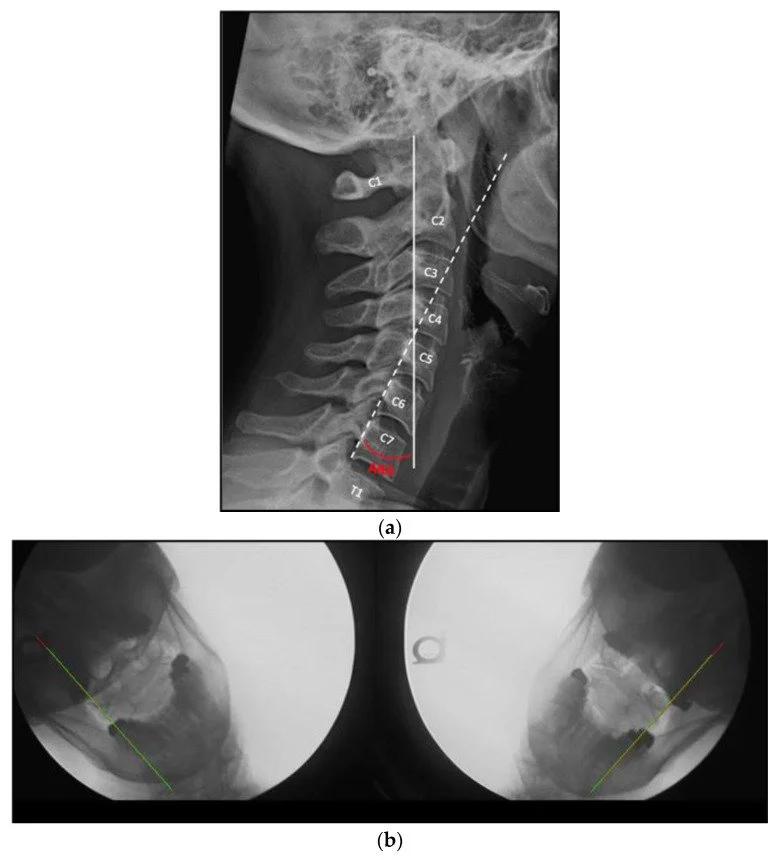

• All nine patients showed radiographic improvements—better cervical curve and reduced upper cervical instability (assessed by C1 lateral-mass overhang on C2 during lateral flexion).

Improvement in lordosis correlated with reduced instability. Regression showed R² = 0.46, p = 0.04, meaning about 46% of instability reduction can be statistically associated with curve correction.

A: They measured C1 lateral mass overhang on C2 during side bending. That overhang decreased as lordosis improved.